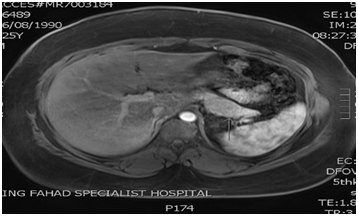

After five months from pancreatic surgery, Patient has been admitted electively after primary hyper parathyrodism localization imaging (Figure 4), to undergo total 4 glands parathyroidectomy and thymoctomy, with half parathyroid gland re implantation in the lower sternothyroid muscle, intraoperative PTH dropped from 236 to 15.5pg/ml, about 90% reduction, post procedure. It was without complication. Follow up Pathology report revealed4 glands hyperplasia.

Figure 4 NM parathyroid (with Sestamibi)

Figure 5 scintigraphic evidence suggestive of hyper functioning left lower parathyroid gland.